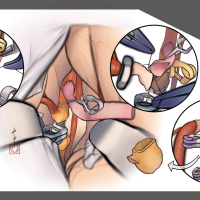

監修:谷川 緑野 / 札幌禎心会病院脳卒中センター

監修:太田 仲郎

監修:永田 雄一